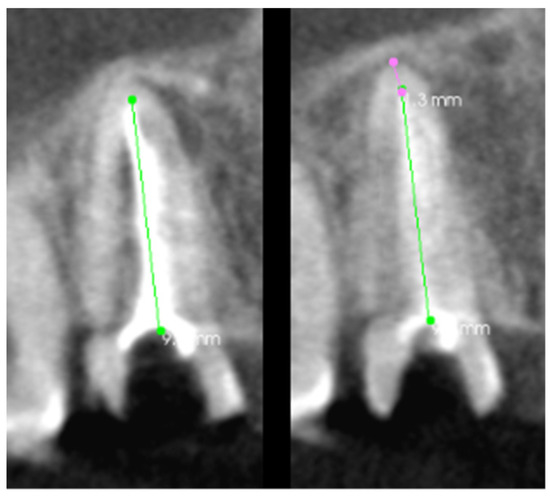

In this case, the patient was referred for endodontic retreatment of tooth 46 due to incomplete canals and the presence of a broken instrument in the mesial lingual canal. The CT scan of the tooth, which was used for the analysis of the root canals in the transverse plane in the case of tooth 46, is shown in Figure 15. The generated 3D model made it possible to determine the exact position of the tool concerning the lingual tubercle and the number of root tissues surrounding the file, as shown in Figure 16. By determining the location of the proximal end of the broken file, access and visibility in the operating microscope were obtained. Munce burs and ultrasonic tips were used for access. Thanks to the precise location provided by the hologram, access was obtained without unnecessary loss of root tissue, which could lead to perforation or root fracture in the future. The broken file was removed using a Miller needle as an ultrasonic tip. The canals were developed and filled with permanent material. This stage of treatment ended with a traditional X-ray. As in the above cases, the visibility of all root canals in the transverse plane was analyzed on individual scans, which are presented in Table 6.

Figure 15. The CT scan of the tooth was used for the analysis of the root canals in the transverse plane, in the case of tooth 46.